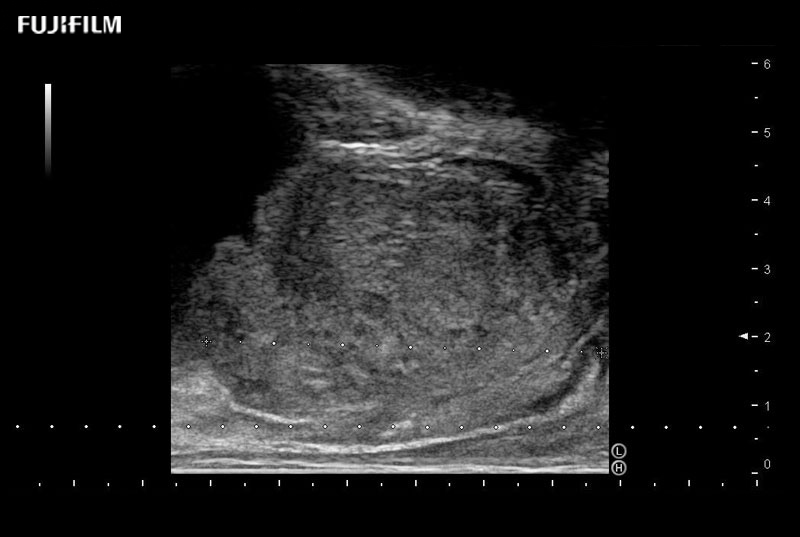

Designed for high-resolution imaging of the scrotal and penile regions. This advanced transducer offers exceptional image quality, user-friendly features, and specialized functionalities to support accurate urological diagnostics and enhance patient care.

Main Specifications: